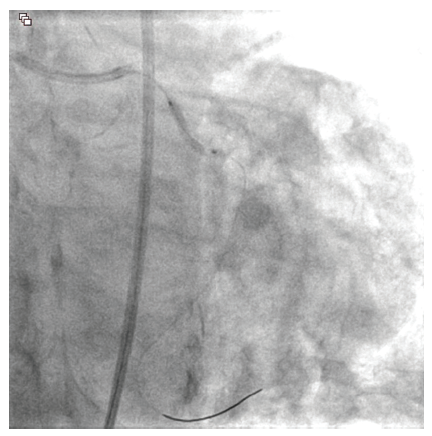

An 81-year-old male with hypertension, diabetes, and hyperlipidemia was referred for evaluation of an abnormal stress test. He originally complained of shortness of breath with exertion. A pharmacologic stress test was performed at an outside facility and showed inferior wall ischemia with a normal ejection fraction. He underwent coronary angiography via a right radial approach that revealed a heavily calcified, eccentric lesion in the large, codominant circumflex artery with TIMI-3 flow (Figure 1). Due to a small ulnar artery, the decision was made to access the right femoral artery in preparation for complex intervention. Utilizing a 6 French Judkins Left 4 guide catheter, the left system was engaged. The lesion was wired with a Runthrough® Izanai™ wire (Terumo Interventional Systems) and pretreated with balloon angioplasty using a 2.0 mm x 15 mm Takeru™ RX balloon (Terumo Interventional Systems) (Figure 2). A 2.5 mm x 15 mm Takeru™ RX noncompliant (NC) balloon was then advanced to perform further pre-dilation balloon angioplasty (Figure 3).